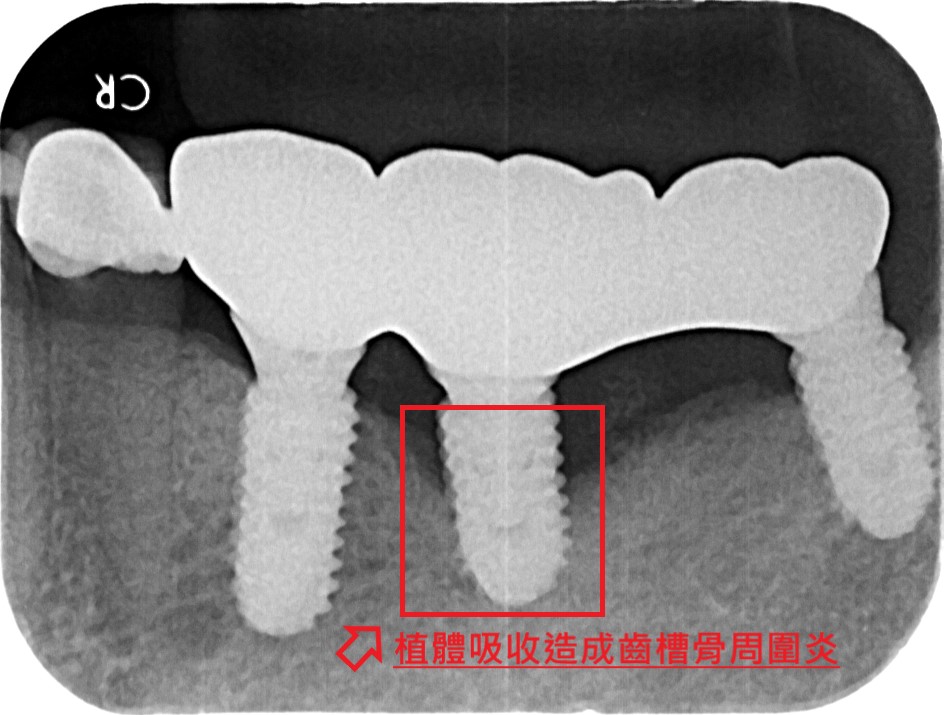

植體周圍炎處理

針對植牙周圍牙齦與骨組織的發炎感染進行清創、消毒與骨再生治療,抑制病菌、減少骨吸收,恢復植牙穩定性並延長使用壽命。